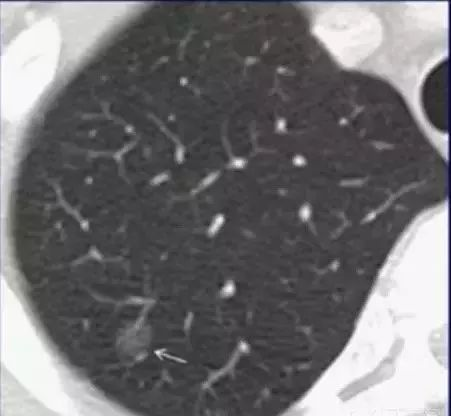

胸部CT上发现的磨玻璃样结节(箭头所示),病理结果为微浸润性腺癌(早期的肺癌),这在胸片上根本看不到。

胸部CT是胸部查体的首选检查。

胸部CT由于其分辨率高,可以发现肺上很小的结节灶,因此胸部CT对于肺癌的早期诊断具有极其重要的价值。而鉴于胸部CT有放射性,遂提出了低剂量胸部CT的概念。